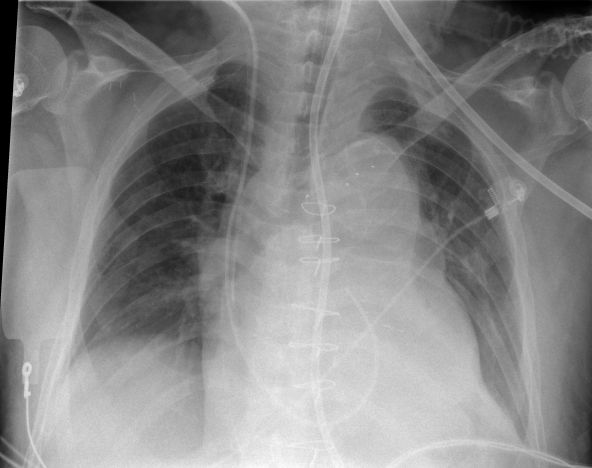

Attaching and de-attaching a grid in urgent care situations adds time and physical effort to the imaging process. This slows the path to diagnosis and increases the chance of error through potential issues like grid misalignment. Gridless X-ray capabilities provide a solution to this challenge, but come with their own set of complications such as an increased likelihood of scattered radiation that negatively impacts image quality.

SkyFlow gridless X-ray reduces the effect of scattered radiation for non-grid bedside chest exams, allowing for DR images with grid-like contrast while avoiding the time and effort of attaching and detaching a grid. SkyFlow identifies scatter signal and automatically applies correction immediately at the bedside, allowing radiologists to review images and make decisions on the spot.

With no grid to attach, SkyFlow scatter correction algorithm achieves the high-image contrasts that lead to a confident clinical diagnosis in emergency settings.